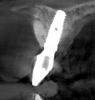

Fig 4. Tomographic images revealed a tridimensional defect extending to the apical third of teeth Nos. 6 and 8, a buccal bone dehiscence on tooth No. 5, and associated thin labial plates.

Figure 4

Tomographic images revealed a large tridimensional defect, with vertical and horizontal loss of bone extending to the apical third of teeth Nos. 6 and 8. Additionally, a buccal bone dehiscence was evident on tooth No. 5, and thin labial plates secondary to the orthodontic movement were present in several areas (Figure 3 and Figure 4).